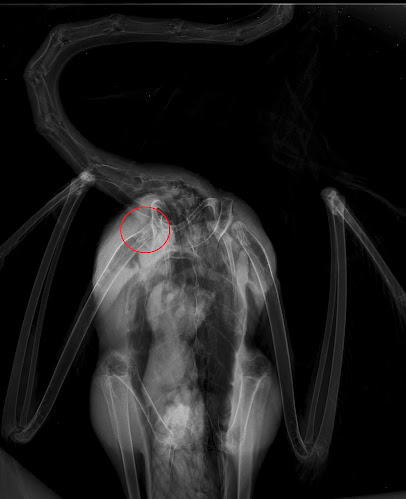

Durante o exame físico, foi possível observar uma luxação no ombro direito confirmada pela realização de um exame radiológico.